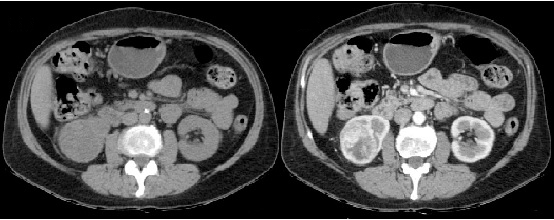

Fase nefrográfica o portal

Se logra a partir de los 80 a 180 segundos posteriores a la inyección del contraste; el medio de contraste se encuentra en los túbulos colectores y asa de Henle durante esta fase y su utilidad se basa en el aumento homogéneo del parénquima renal, lo que permite una mejor delimitación de la masa renal.

Durante esta fase se presenta el mayor realce de los tumores sólidos, por lo que se logra una mejor caracterización de las masas indeterminadas. En un estudio sobre la caracterización de las masas renales menores a 3 cm se concluyó que durante las exploraciones en fase nefrográfica se permitió una mayor detección de lesiones y una mejor caracterización de las masas renales pequeñas que en las exploraciones de fase corticomedular 3-5 (Fig. 3).